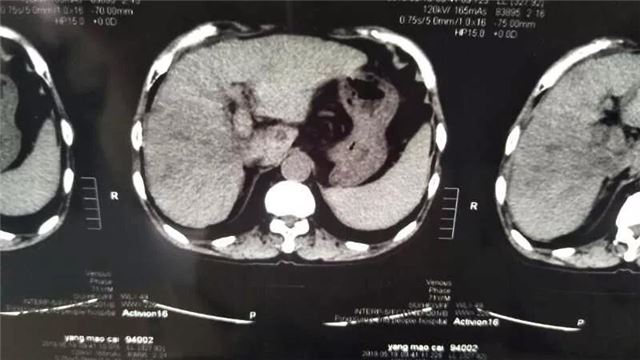

车教授根据CT及生化检查结果告知患者家属:患者肝右叶原发性肝癌并肝内多发转移可能性大,门静脉癌栓形成,先做一期介入治疗:肝癌供血动脉化疗+栓塞术。家属非常支持和配合。

术前

由于患者肝癌较大,肝内多发转移,而且门静脉癌栓形成,病灶恶性程度高,进展快,必须围追堵截,一招致胜。手术中,车教授灵活运用传统和现代肝癌TACE治疗相结合的办法:C-TACE加D-TACE同时运用,即碘油乳化抗癌药(C-TACE)和微球搭载抗癌药(D-TACE)吡柔比星栓塞肿瘤供血动脉,基本阻断癌肿供血动脉,以期慢慢饿死肿瘤。